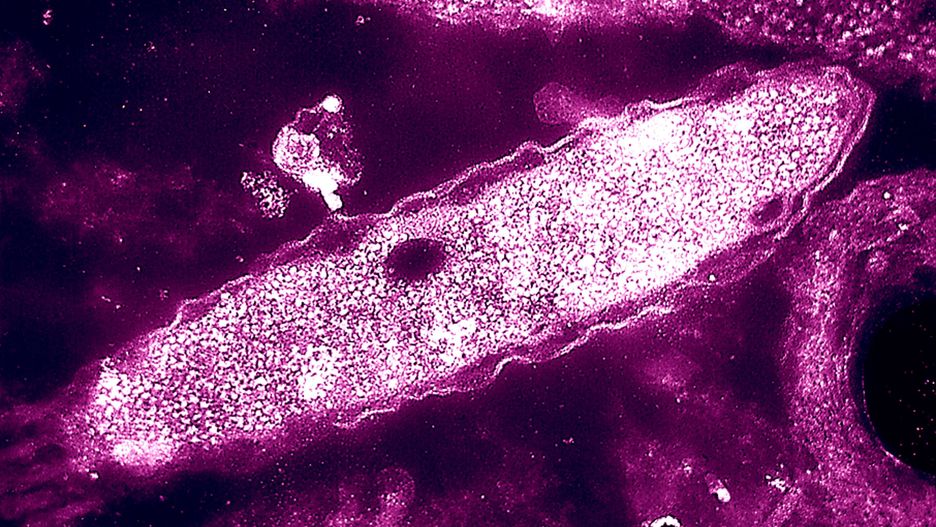

Źródło zdjęć: © PAP | BSIP